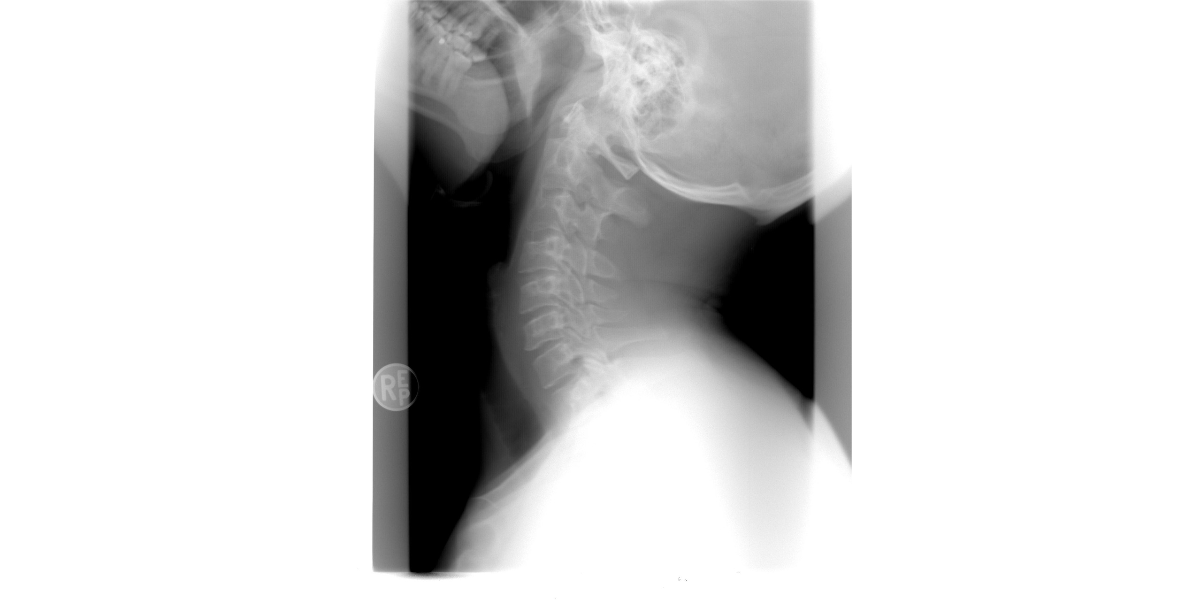

거북목, 혹은 일자목이라고 불리는 이 증상은 말 그대로 목뼈가 앞으로 쏠리면서 마치 거북이처럼 고개가 빠져나온 자세를 말합니다. 정면에서 봤을 때 머리가 어깨보다 앞으로 나가 있거나, 옆에서 봤을 때 목이 직선처럼 서 있다면 거북목을 의심해 볼 수 있습니다. 대표적인 증상은 목 뒤의 뻐근함과 뻣뻣함입니다. 특히 오랜 시간 앉아서 일한 뒤 오후쯤 되면 목이 무겁고, 움직일 때 통증이 생기는 경우가 많습니다. 또한, 어깨와 승모근이 단단히 뭉치고 두통까지 동반되기도 하죠. 더 심한 경우에는 팔이나 손 저림, 눈의 피로, 만성 피로감까지 느낄 수 있습니다. 증상이 더 진행되면 단순한 근육통을 넘어 경추 디스크로 발전할 수도 있습니다. 이 경우 목뼈 사이의 디스크가 신경을 압박하게 되면서 팔 저림, 감각 저하, 집중력 저하 등의 신경 증상이 나타납니다. 이런 경우 단순한 마사지나 파스 같은 일시적 대처로는 해결되지 않으며, 정확한 진단과 치료가 필요합니다.

거북목은 초기에 관리하면 비교적 쉽게 개선이 가능합니다. 먼저, 통증이 지속되거나 일상생활에 지장을 줄 정도라면 병원을 방문해 정확한 진단을 받는 것이 우선입니다. 정형외과나 재활의학과에서는 X-ray, 초음파 등을 통해 경추의 정렬 상태를 확인한 후 치료 방법을 안내합니다. 치료는 일반적으로 물리치료, 도수치료, 그리고 자세교정 운동으로 진행됩니다. 물리치료는 전기 자극이나 온열 요법을 통해 근육의 긴장을 완화시켜 주며, 도수치료는 치료사가 손으로 직접 경추와 어깨를 교정해 줍니다. 하지만 치료보다 더 중요한 것은 ‘예방’입니다. 평소 컴퓨터를 사용할 때 모니터는 눈높이와 수평이 되도록 조정하고, 허리와 등을 바르게 세우는 습관을 들여야 합니다. 또한, 정기적으로 스트레칭을 통해 경직된 근육을 풀어주는 것이 좋습니다. 대표적인 스트레칭으로는 턱 당기기 운동, 어깨 돌리기, 목 옆 근육 늘리기 등이 있으며 하루 3번, 5분씩 실천해도 큰 도움이 됩니다. 기구 활용도 좋은 방법입니다. 자세 교정 의자, 경추 전용 베개, 스탠딩 데스크, 자세 알림 앱 등을 활용하면 무의식 중에도 자세에 대한 인식을 높일 수 있습니다. 무엇보다 중요한 것은 내 몸의 신호를 무시하지 않고, 통증이 시작되는 시점에서 바로 관리에 들어가는 것입니다.